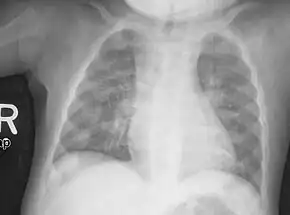

An X-ray or radiograph of an advanced sufferer from rickets tends to present in a classic way: the bowed legs (outward curve of long bone of the legs) and a deformed chest. Changes in the skull also occur causing a distinctive "square headed" appearance known as "caput quadratum".[14] These deformities persist into adult life if not treated. Long-term consequences include permanent curvatures or disfiguration of the long bones, and a curved back.[15]

- Radiography typically show widening of the zones of provisional calcification of the metaphyses secondary to unmineralized osteoid. Cupping, fraying, and splaying of metaphyses typically appears with growth and continued weight bearing.[36] These changes are seen predominantly at sites of rapid growth, including the proximal humerus, distal radius, distal femur and both the proximal and the distal tibia. Therefore, a skeletal survey for rickets can be accomplished with anteroposterior radiographs of the knees, wrists, and ankles.[36]